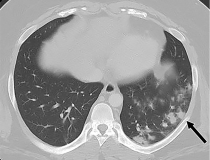

This photo gallery shows the variety of radiological presentations of COVID-19 (SARS-CoV-2) in medical imaging, including computed tomography (CT), radiograph X-rays, ultrasound, echocardiograms and magnetic resonance imaging (MRI). The radiology images show examples of typical COVID pneumonia in the lungs and the numerous complications the virus causes in the body in multiple organs, including the brain, kidneys, heart, abdomen and vascular system.

Ultrasound, especially hand-held ultrasound imaging devices, have become a primary imaging modality for novel coronavirus because of the ease to bag the device and sterilize it after use. CT and mobile X-ray systems are also used as front-line imaging systems for COVID-positive or suspected COVID patients.